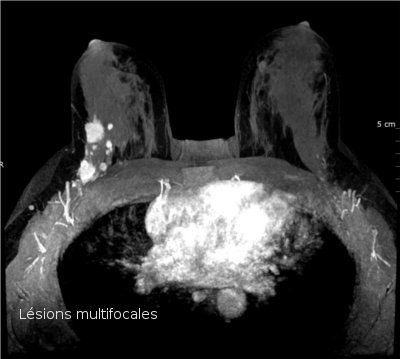

- si une lésion cancéreuse volontiers multifocale ou bilatérale (cancer de type lobulaire par exemple) a été diagnostiquée, pour rechercher une autre lésion non décelée par la mammographie avec échographie.